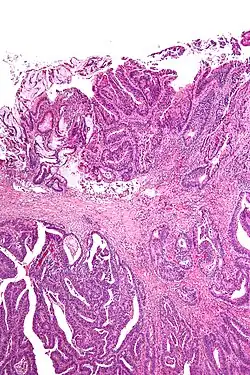

A resection margin or surgical margin is the edge or "margin" of apparently non-tumorous tissue around a tumor that has been surgically removed, called "resected", in surgical oncology. The resection is an attempt to remove a cancer tumor so that no portion of the malignant growth extends past the edges or margin of the removed tumor and surrounding tissue. These are retained after the surgery and examined microscopically by a pathologist to see if the margin is indeed free from tumor cells (called "negative"). If cancerous cells are found at the edges (called "positive") the operation is much less likely to achieve the desired results.[1]: sections 1-2

Surgical margin in a surgery report defines the visible margin or free edge of "normal" tissue seen by the surgeon with the naked eye. Surgical margin as read in a pathology report defines the histological measurement of normal or unaffected tissue surrounding the visible tumor under a microscope on a glass mounted histology section.[4][5] A "narrow" surgical margin implies that the tumor exists very close to the surgical margin, and a "wide" surgical margin implies the tumor exists far from the cut edge or the surgical margin. Narrow surgical margin using the bread loafing technique suggests that residual cancer might be left due to false negative error. A surgeon often will perform a second surgery if a narrow surgical margin is noted on a pathology report.